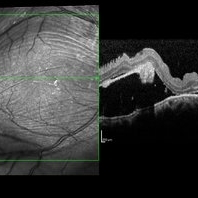

Vogt Koyanagi Harada

Oct 7 2015 by Avris Romario Diparaja Siahaan

A FA and OCT of a 42-year-old woman with Harada Syndrome in both eyes.

Photographer: Yohanes Harry Purwanto, Klinik Mata Nusantara

Imaging device: Heidelberg HRA + OCT

Condition/keywords: optical coherence tomography (OCT), Vogt-Koyanagi-Harada